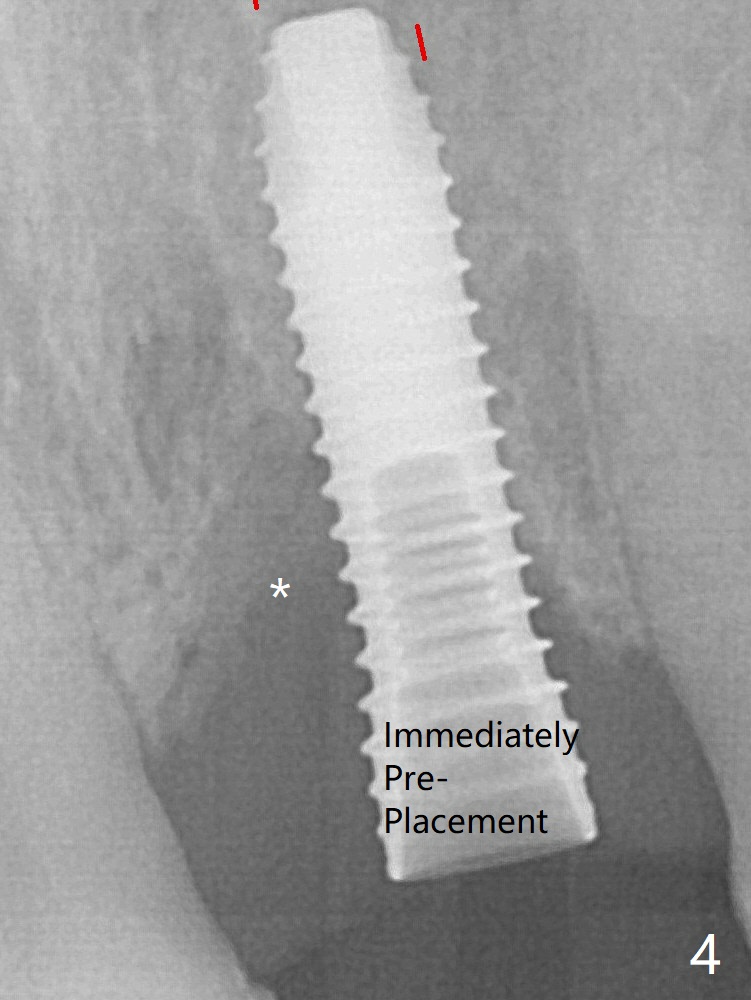

Note the size of the mesial defect before complete seating a 3.8x15 mm dummy implant (Fig.4 *). The defect is filled with Vera Graft (Fig.7 *) and heals 1 year 4 months postop (Fig.11).